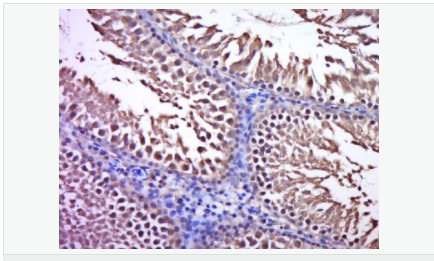

Expressed in enterocytes of small and large intestinal mucosa (at protein level). Expressed in enterocytes, chromaffine and interstitial cells.